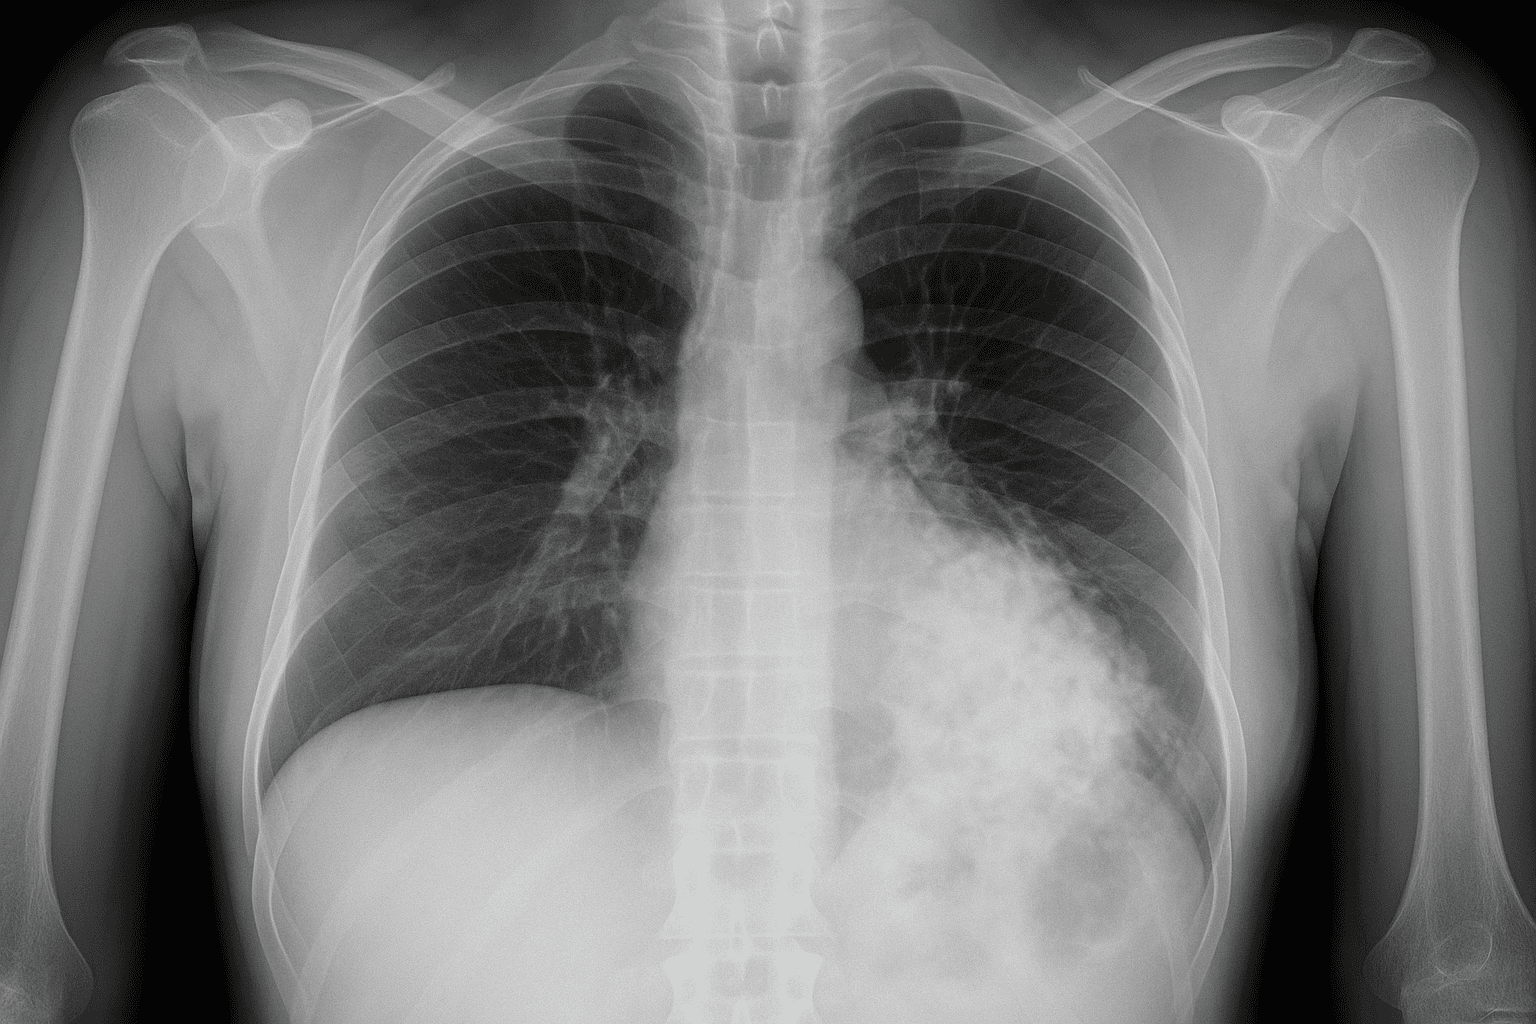

胸部X線(肺の異常陰影)

胸部レントゲン検査では肺や心臓の状態を調べます。

正常では写らない影が認められた場合、「要経過観察」あるいは異常の疑いとして再検査が必要になります。少しでも異常が疑われれば健診結果では通常「要精密検査」(D判定相当)と判断され、追加の検査(例えば胸部CT撮影)が推奨されます。

胸部X線で指摘される影は、多くは過去の炎症痕や良性の変化である場合もありますが、肺結核や肺炎、肺がんなど重篤な病気の可能性も否定できません。

実際に胸部レントゲンで異常が見つかったケースのうち、肺がん等の重大疾患が判明する割合はごく一部とはいえ、見逃すと命に関わるため注意が必要です。

結核のように感染性の疾患の場合は周囲への影響も大きいため、疑わしい所見があれば速やかに精密検査で確定診断を行い、必要なら治療・隔離などの対応を取る必要があります。

胸部X線で異常を指摘された新入社員は、不安があっても早急に医療機関で胸部CTなどの精密検査を受けて原因を確認することが望まれます。